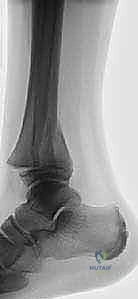

- الأشعة السينية (X-rays): هي الخطوة الأولى والأساسية. يتم التقاط صور من زوايا متعددة (أمامية، جانبية، ومائلة) لتقييم الكسر.

- الأشعة المقطعية ثلاثية الأبعاد (3D CT Scan): تُعد ضرورة حتمية في حالات كسور تيلوكس والكسور ثلاثية المستويات، أو أي كسر يمتد داخل المفصل. توفر الأشعة المقطعية خريطة دقيقة لحجم القطع العظمية ومقدار التباعد (Displacement)، مما يساعد في التخطيط الجراحي المسبق.

- الكسر ثلاثي المستويات (Triplane Fracture): كسر شديد التعقيد يمر عبر ثلاثة مستويات مختلفة (سهمي، إكليلي، وعرضي). يظهر في الأشعة الأمامية ككسر سالتر-هاريس من النوع الثالث، وفي الأشعة الجانبية ككسر من النوع الثاني. يتطلب هذا الكسر دائمًا فحصًا مقطعيًا (CT Scan) لتقييمه بشكل صحيح.